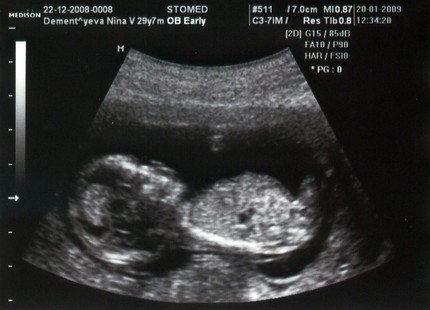

Photo échographie: